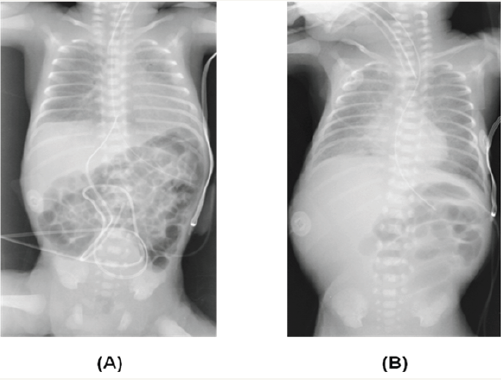

Unlike older children, imaging modalities such as plain abdominal films, contrast enemas and abdominal ultrasounds are not very helpful in making a diagnosis of intussusception in preterm infants [2,4-6]. Lack of bowel gas in the right lower quadrant, as in our case, has been described in other preterm infants with intussusception but is an inconsistent finding (Figure 1) [1,8,12]. Although contrast enemas may be both diagnostic and therapeutic in older infants, they are not helpful in preterm infants as intussusception in preterm infants is almost always confined to the small intestine, unlike older infants where it is usually ileocolic [5,6,8,12]. Some investigators have in fact recommended that contrast enemas should be avoided in preterm infants, as they increase the risk for perforation [5,6]. In older infants, abdominal ultrasound has a sensitivity of over 98% and specificity of 100% in the diagnosis of intussusception [11,12]. In our review of intussusception in preterm infants, of the 35 or so reported cases, only two were diagnosed with abdominal ultrasound [2]. The lack of efficacy of abdominal ultrasound in diagnosing intussusception in preterm infants may again be due to the absence of colonic involvement in preterm infants [4,11]. However, ultrasound is an easy to use, non-invasive, bedside investigation and in an effort to make an early diagnosis, should be considered in any neonate suspected to have intussusception [2].

Figure 1: Abdominal x-ray of the infant.

A) Day two of life demonstrating a symmetrical gas pattern.

(B) Day 10 of life showing an asymmetrical gas pattern with paucity of gas in the right lower quadrant.